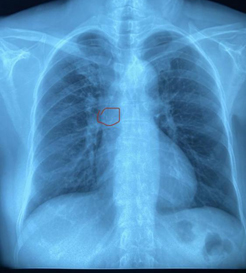

• “偏心”少年选择瑞康

人们常说,人都是偏心的,因为心脏原本就是偏左的。其实偏右的心脏也算偏心,它有个医学名叫“右位心。”它的位置好像照镜子时所见一样,呈镜像对...